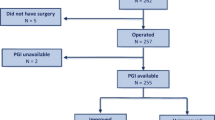

A cross-sectional observational study was performed, enrolling consecutive women seeking cares for lower urinary tract symptoms (LUTS) with evidence of POP. Data regarding baseline characteristics, LUTS, and physical examination were gathered for each patient. Multivariate analysis (multiple linear regression (MLR)) and artificial neural networks (ANNs) were performed to design predicting models.